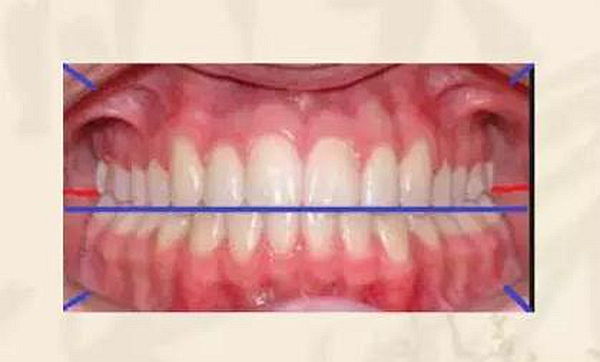

圖文詳解正畸的拍照細(xì)則 科貿(mào)嘉友收錄

來(lái)源:李筱筱 正畸學(xué)會(huì)